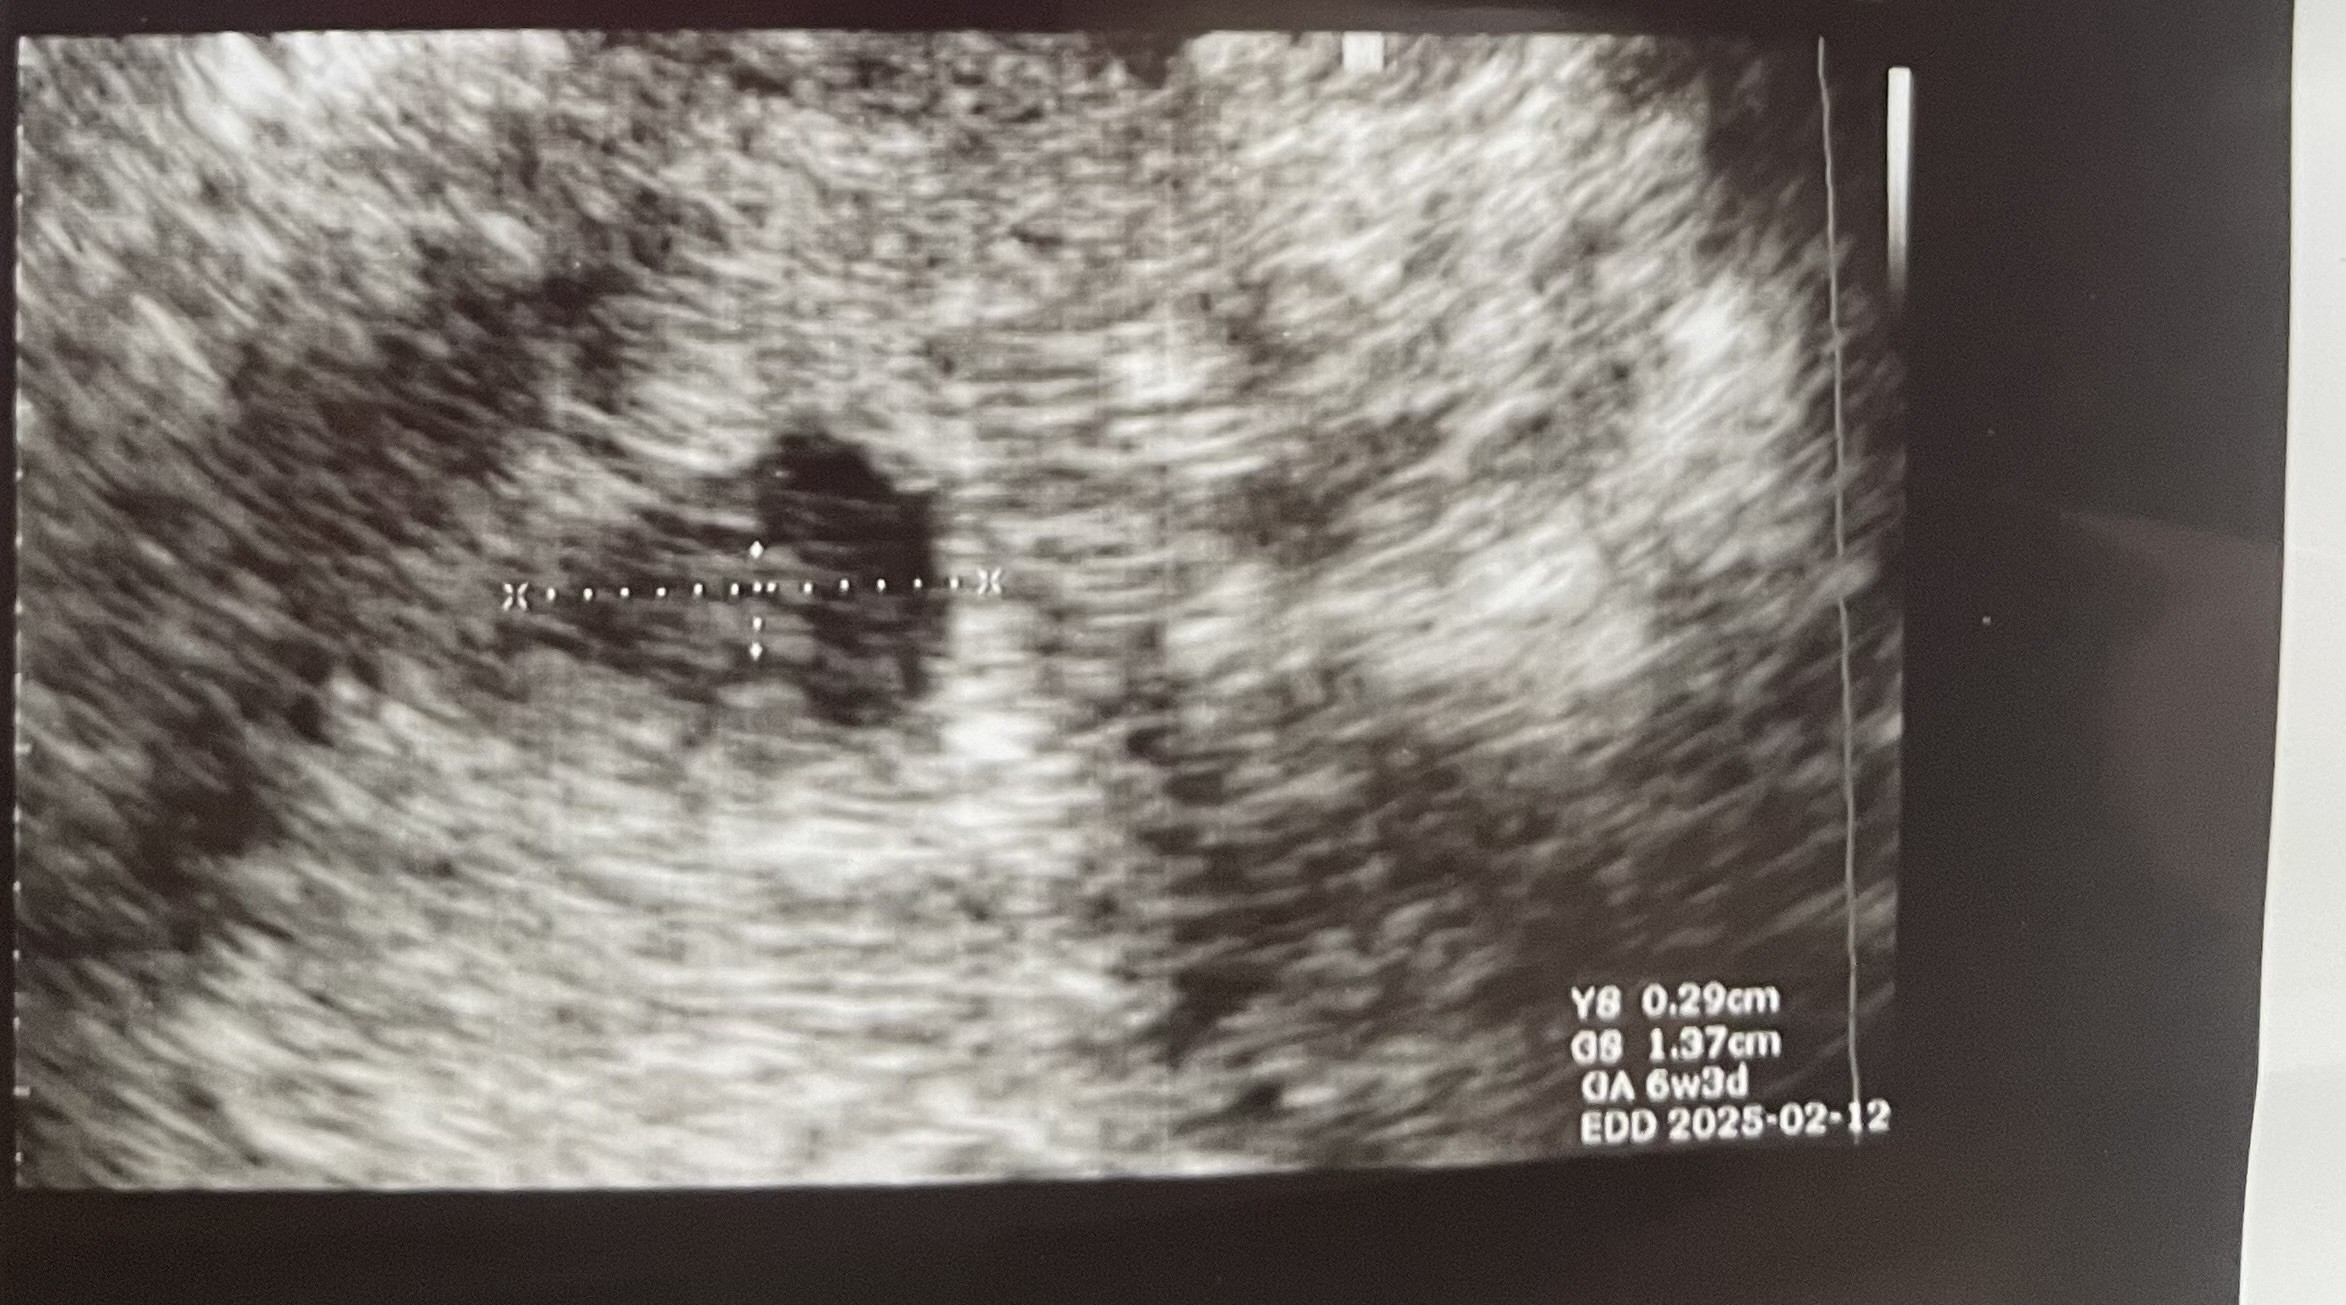

Dziewczyny jestem po usg. 6 tydzień i 3 dzień. Ciulowo widać bo lekarz ma słabe USG, chyba stare już 🤭 umówiliśmy się na piątek na ponowne usg i żeby posłuchać serduszka.

Załączniki

• IMG_5899.jpeg

IMG_5899.jpeg

714 KB · Wyświetleń: 65